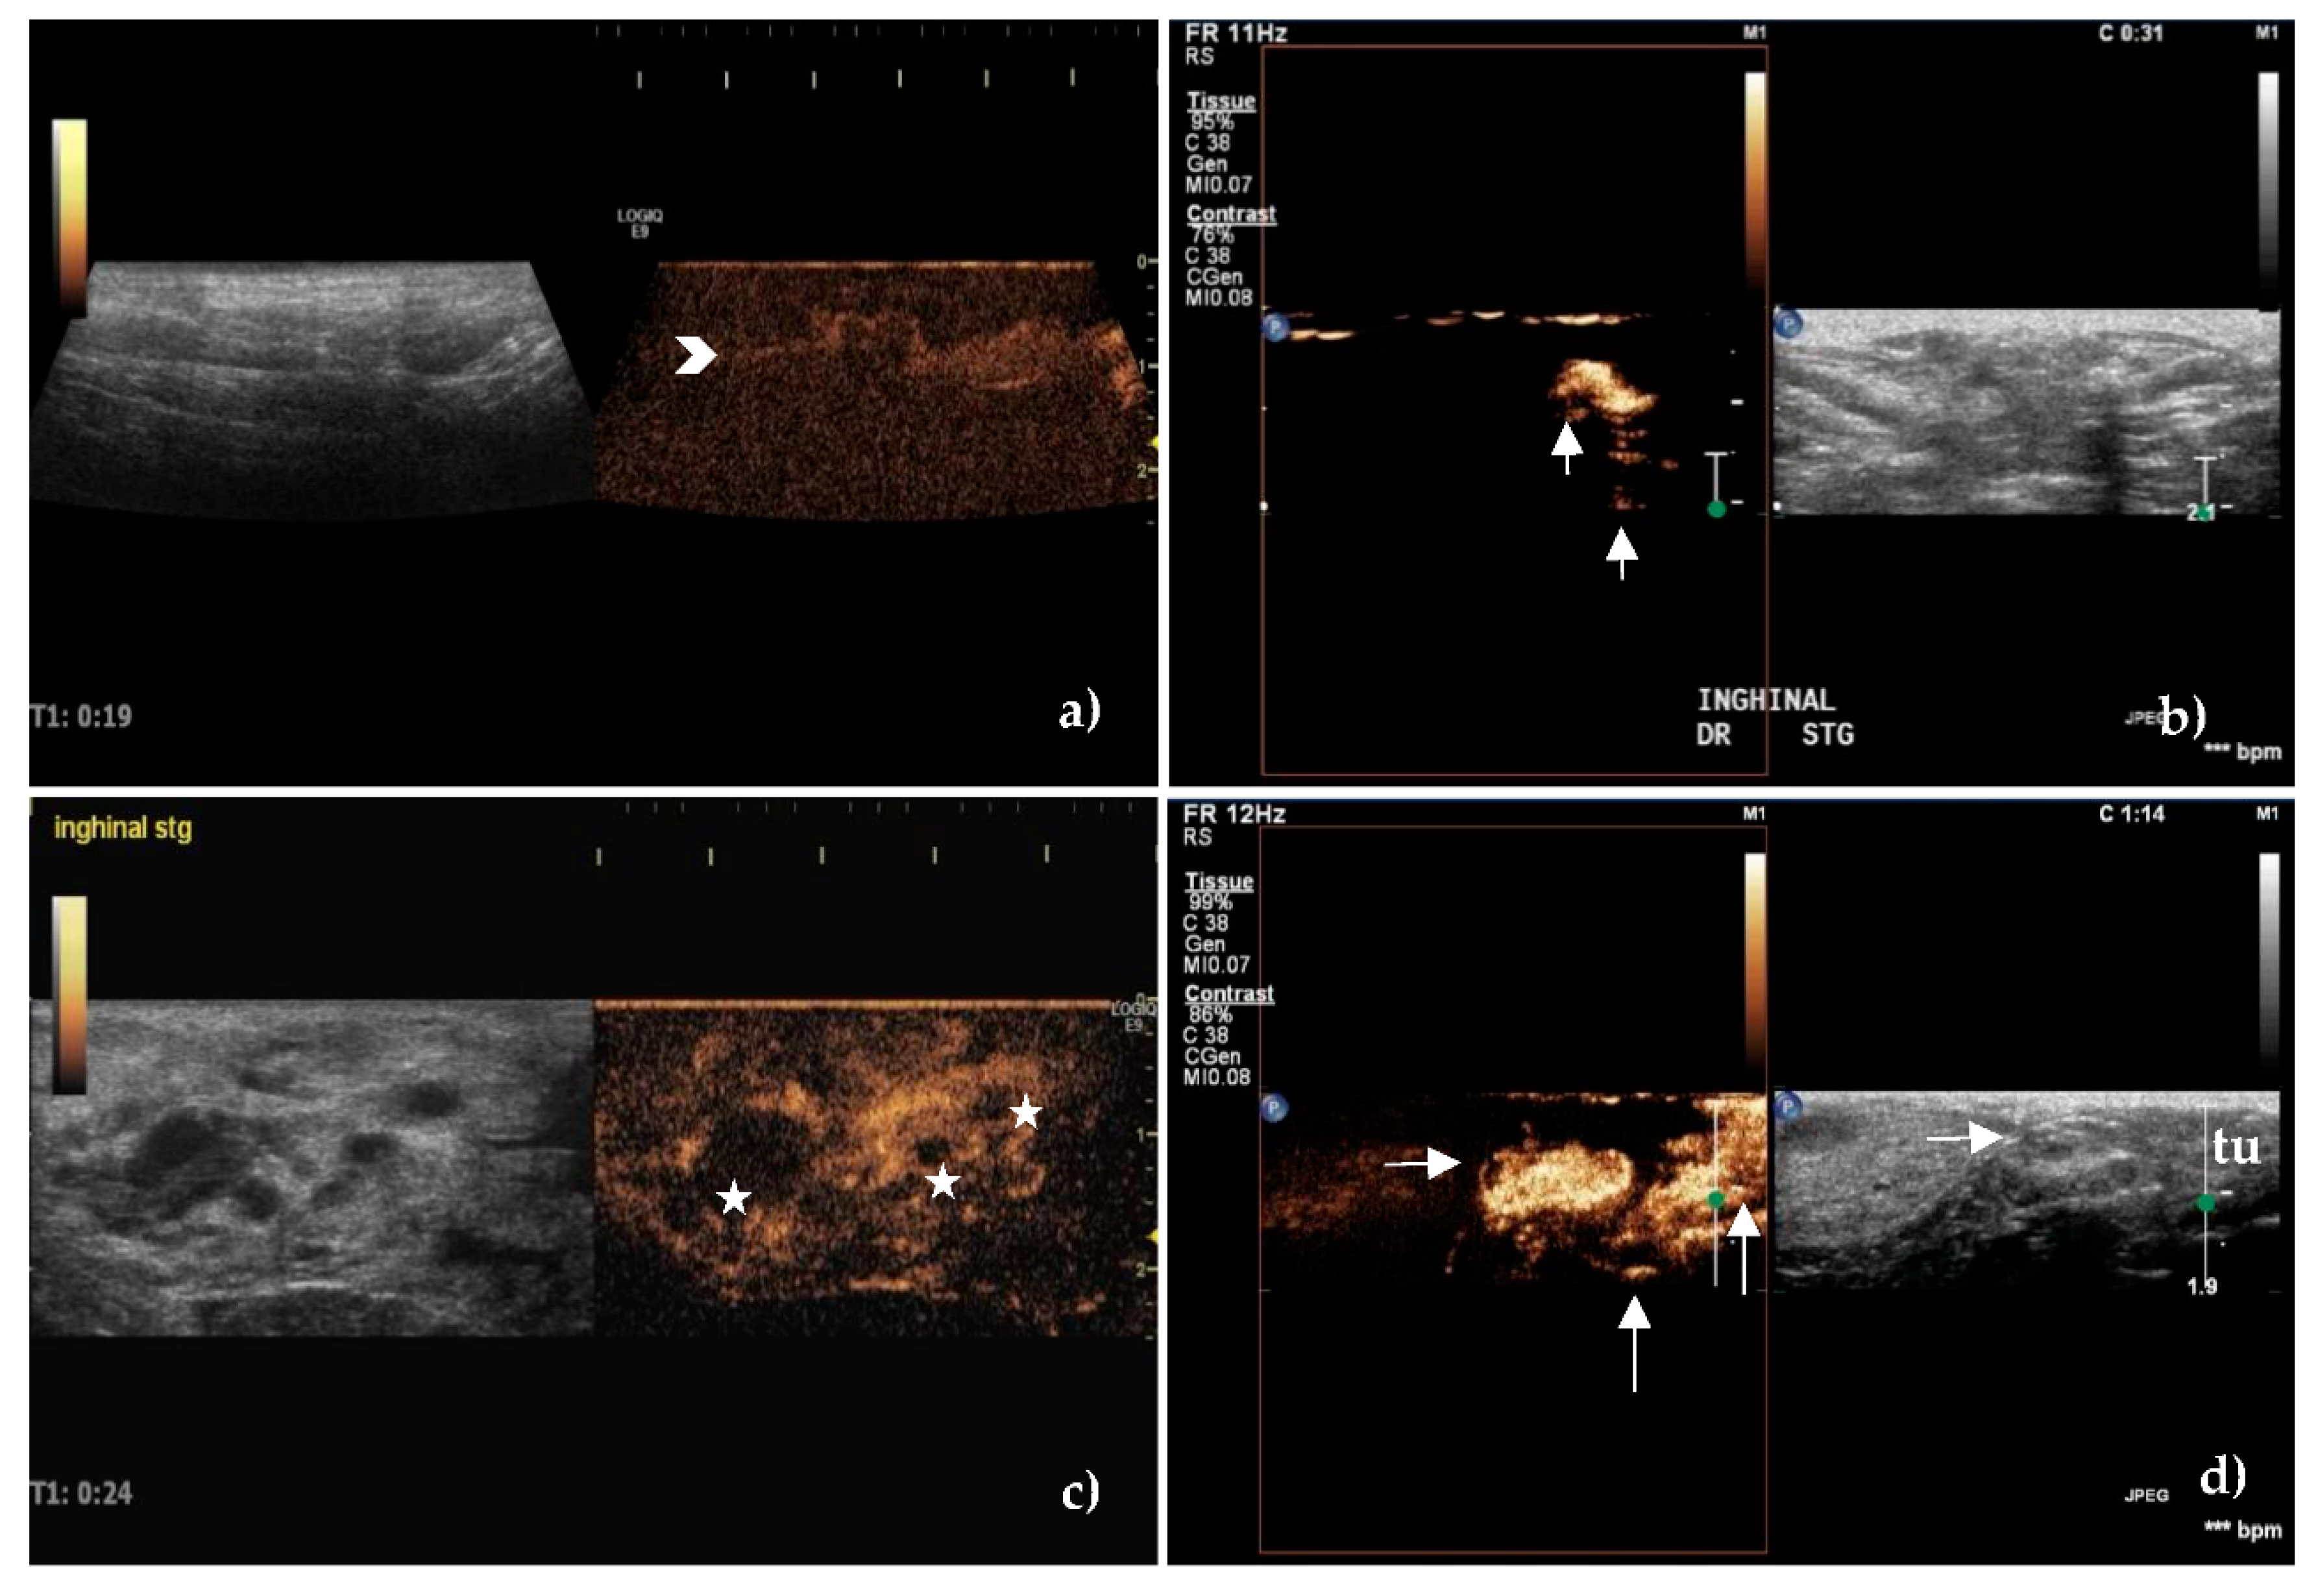

The Doppler technique certified the presence of a vascular signal in 40 unaffected SLNs and 53 metastatic SLNs, with different pattern between the groups, p < 0.001.

In 85.71% of non-metastatic SLNs, blood vessels started from the hilum and were orderly distributed toward the capsule (Figure 2a,b), whereas in 88.88% of the metastatic SLNs, the vascularization had a disordered, chaotic appearance, with predominantly peripherally location (55.55%) or mixed (20.37%) (Figure 2c,d). 12 metastatic SLNs had a perfused hilar region.

Figure 2. Vessels location and distribution assessed by Color Doppler ultrasound. (a) Central, hilar vessels of unaffected superficial inguinal sentinel lymph node and (b) unaffected axillary sentinel lymph node. (c) Presence of neovascularisation with an abnormal, hilar, and peripheral distribution of vessels in a metastatic superficial inguinal sentinel lymph node. (d) Mixed hilar and peripheral pattern with the parenchymal subcapsular location of vessels in a metastatic axillary sentinel lymph node.

After peritumoral injection of SonoVue, the lymphatic vessels were identified as hyperechoic and well-defined linear structures Initially, the route of the lymphatic vessels was superficial, then became deeper close to the SLNs (Figure 4).

Figure 4. Contrast-enhanced ultrasound of sentinel lymph nodes after peritumoral administration of contrast agent. (a) Complete, homogeneous enhancement of an unaffected axillary sentinel lymph node with an evident hyperechoic lymphatic vessel—chevron arrow. (b) Intense enhancement of an unaffected superficial inguinal sentinel lymph node. Note the lymphatic vessels that bypass the lymph node leading to the next lymph node station—vertical arrows. (c) Inhomogeneous enhancement of a metastatic superficial inguinal sentinel lymph node. Areas with enhancement defects are present—stars. (d) The focal cortical area with no enhancement—horizontal arrow, of a metastatic superficial inguinal sentinel lymph node located in the vicinity of a tumor (tu) of the inguinal mammary gland. Note the multiple afferent lymphatic channels as hyperechoic linear structures that approach the lymph node and the contrast agent that was injected peritumorally—vertical arrows.

Three types of lymph node enhancement have been established: 1. intense or moderate but homogeneous enhancement without areas with no contrast; 2. inhomogeneous or partially inhomogeneous with the presence of areas without contrast, either peripherally or centrally, and 3. no enhancement.

The enhancement patterns were quantified as intense, centripetal, homogeneous, without enhancement defects in most unaffected SLNs (76.19%), belonging to type 1, (Figure 4a,b) compared to the inhomogeneous pattern (81.48%), with the presence of areas with no contrast in the metastatic ones (p < 0.001), belonging to type 2 (Figure 4c,d).